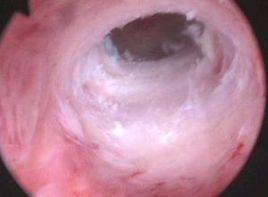

宫腔粘连b超图片最新

宫腔粘连b超图片最新,宫腔粘连b超图片

宫腔粘连

宫腔粘连图片宫腔镜

宫腔粘连图片

宫腔粘连高清图片

轻度宫腔粘连图片

重度宫腔粘连图片

宫腔粘连宫腔镜